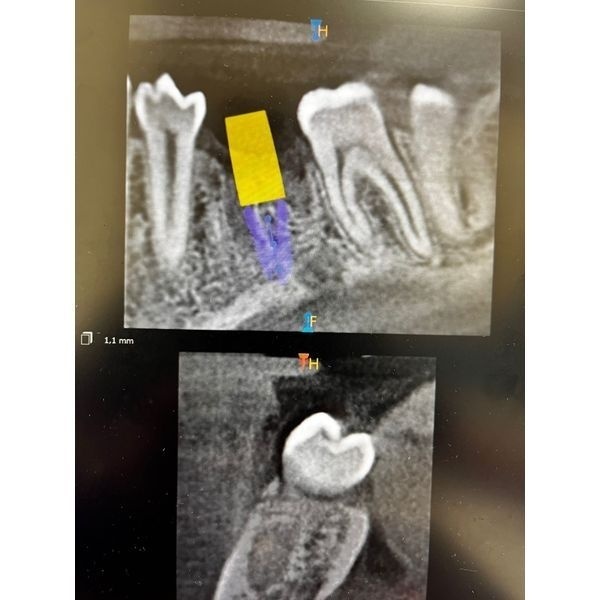

КТ нижней челюсти показала:

- ширина в планируемом месте постановки имплантата приблизительно 10 мм;

- высота до нижнего альвеолярного нерва — 14 мм;

- расстояние между зубами 3.5 и 3.7 — 13 мм.